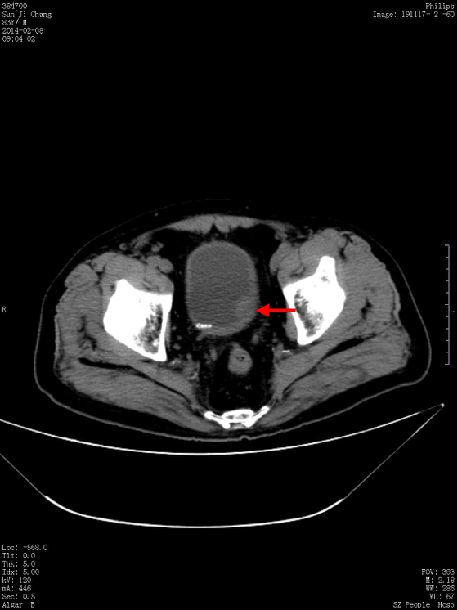

ct52814:膀胱占位

术前ct见膀胱左侧壁占位.